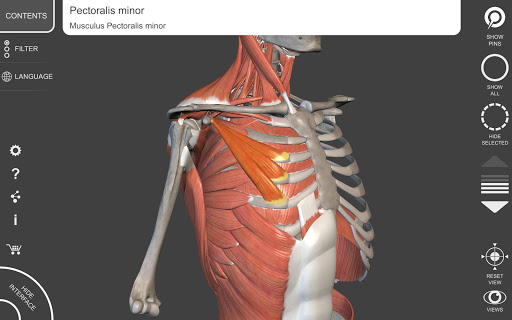

"Anatomy 3D Atlas" memungkinkan Anda mempelajari anatomi manusia dengan cara yang mudah dan interaktif.

Melalui antarmuka yang sederhana dan intuitif, Anda dapat mengamati setiap struktur anatomi dari sudut mana pun.

Model 3D anatomi sangat terperinci dan memiliki tekstur hingga resolusi 4k.

MODEL ANATOMI 3D

• Sistem muskuloskeletal

saraf • Sistem pernapasan • Sistem pencernaan • Sistem urogenital (pria dan wanita) • Sistem endokrin • Sistem limfatik • Sistem mata dan telinga FITUR • Antarmuka yang sederhana dan intuitif • Putar dan perbesar setiap model dalam ruang 3D • Opsi untuk menyembunyikan atau mengisolasi satu atau beberapa model yang dipilih • Filter untuk menyembunyikan atau menampilkan setiap sistem • Fungsi pencarian untuk menemukan setiap bagian anatomi dengan mudah • Fungsi penanda untuk menyimpan tampilan khusus • Rotasi cerdas yang menggerakkan pusat rotasi secara otomatis • Fungsi transparansi • Visualisasi otot melalui tingkat lapisan dari yang superfisial hingga yang terdalam • Dengan memilih model atau pin, istilah anatomi terkait akan muncul • Deskripsi otot: asal, • Tampilkan/ Sembunyikan antarmuka UI (sangat berguna dengan layar kecil) MULTIBAHASA • Istilah anatomi dan antarmuka pengguna tersedia dalam 11 bahasa: Latin, Inggris, Prancis, Jerman, Italia, Portugis, Turki, Rusia, Spanyol, Mandarin, Jepang, dan Korea • Istilah anatomi dapat ditampilkan dalam dua bahasa secara bersamaan PERSYARATAN SISTEM • Android 8.0 atau yang lebih baru, perangkat dengan RAM minimal 3GB Reversi